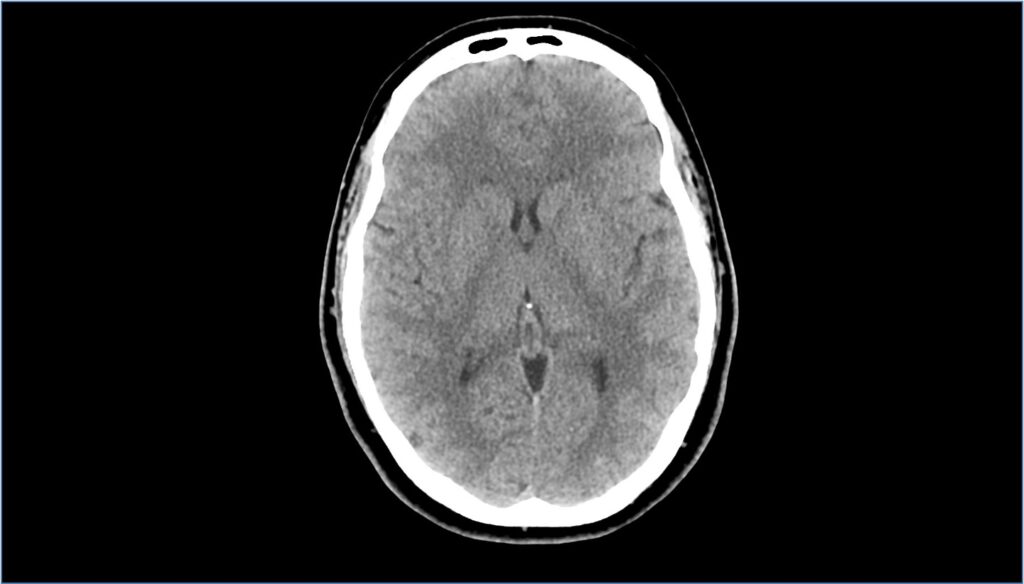

TC encefalo o del capo

Cos’è? La TC encefalo/del capo è un esame diagnostico usato per ottenere immagini dettagliate delle strutture e dei tessuti che compongono la testa. L’esame può